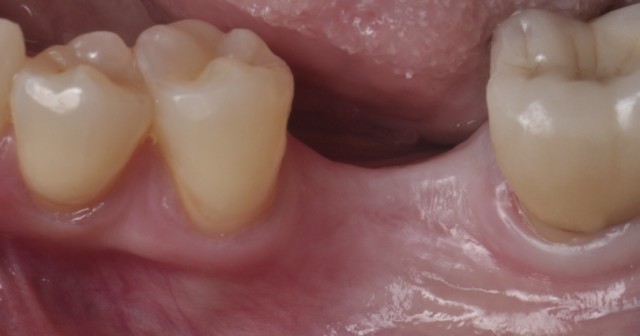

Comprehensive Alveolar Ridge Augmentation and Implant Placement: A Case Study

Post-extraction alveolar ridge shrinking can jeopardize the patient’s oral health, but bone and epithelial grafting can support long-term implant success.By Gonzalo Blasi